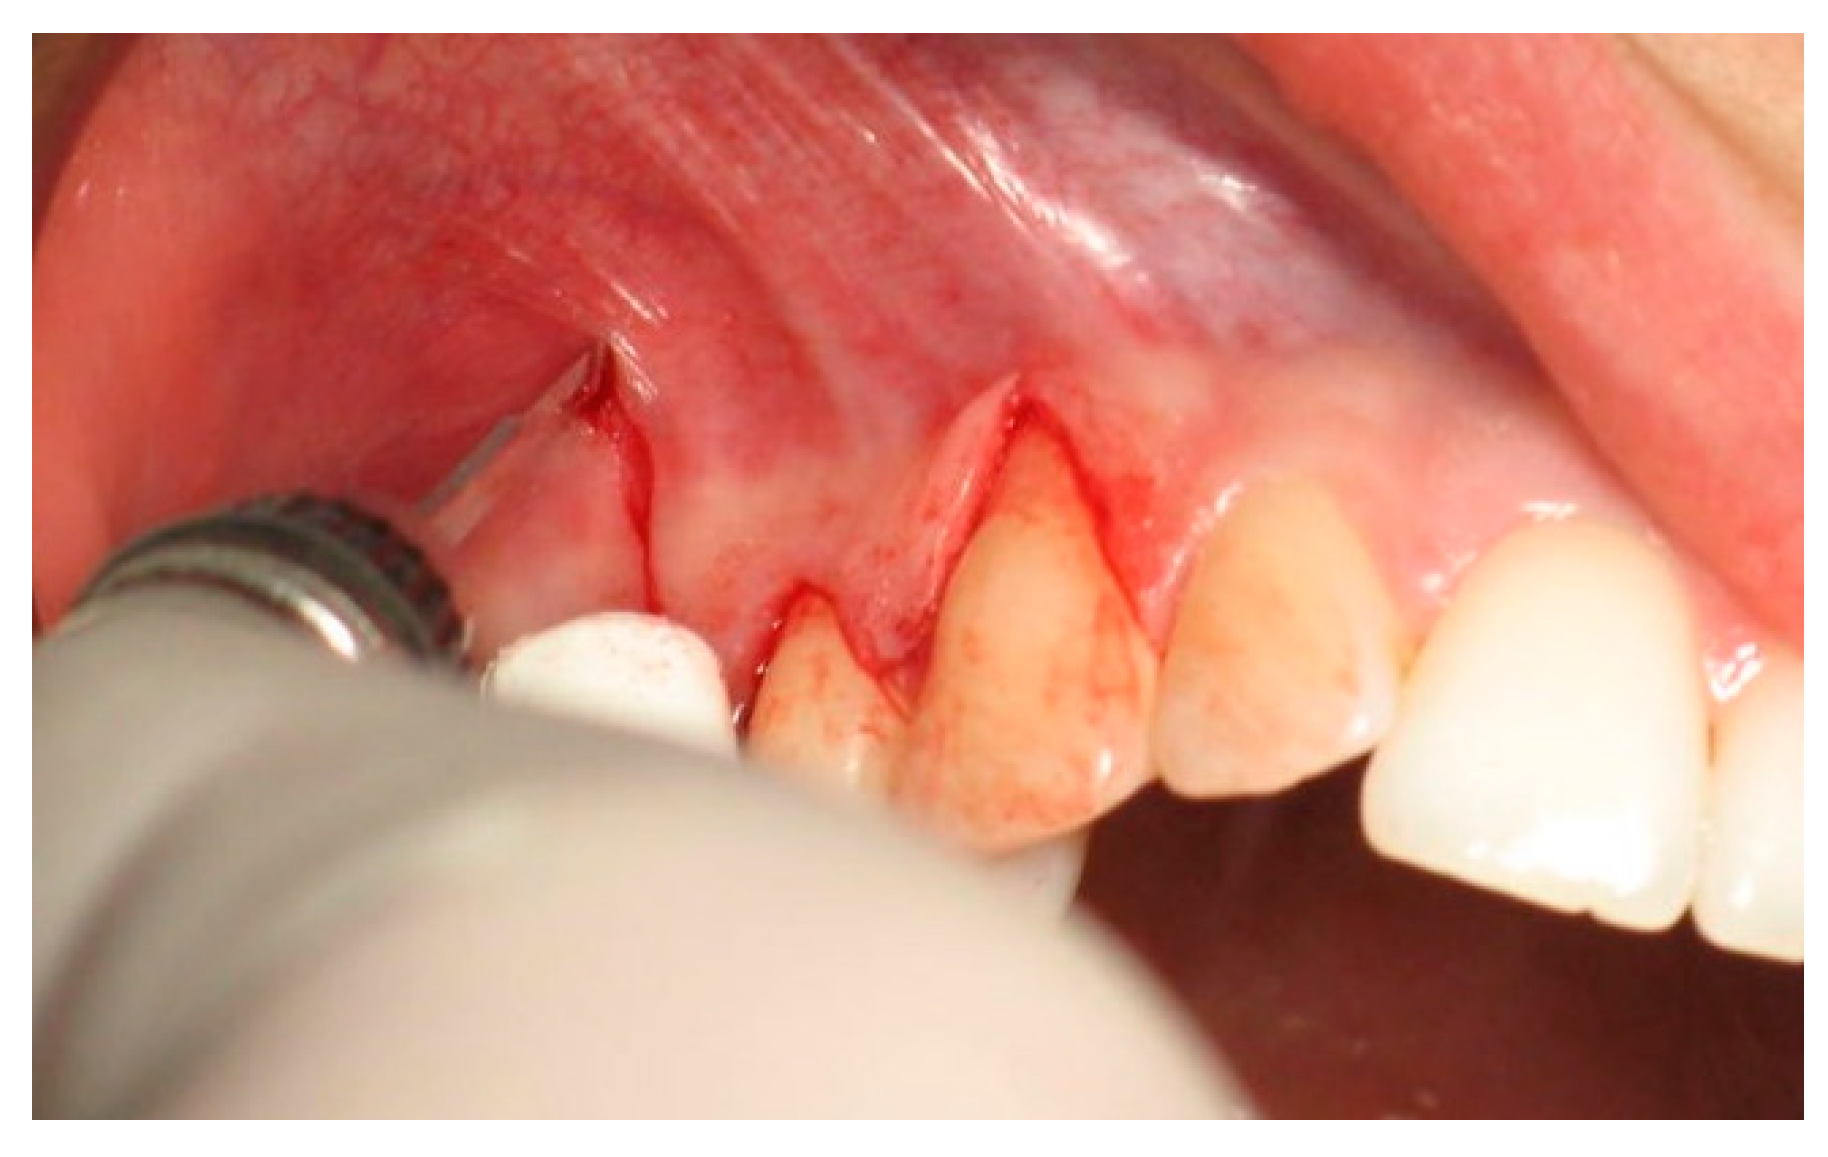

:1. Introduction

2. Materials and Methods

2.3. Surgical Procedures